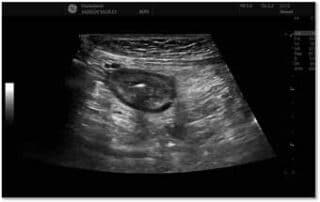

Endoskopisk ultralyd som presisjonspresisjonsverktøy ved pankreaskreft – erfaringer fra en norsk populasjonpopulasjonsbasert studie (NORPACT-2)

Endoskopisk ultralyd (EUS) har etablert seg som et helt sentralt ledd i diagnostikk og behandlingsstrategi ved pankreaskreft. Gjennom EUS-veiledet finnålsaspirasjon (FNA) eller biopsi (FNB) kan man sikre histologisk diagnose med høy presisjon, [...]